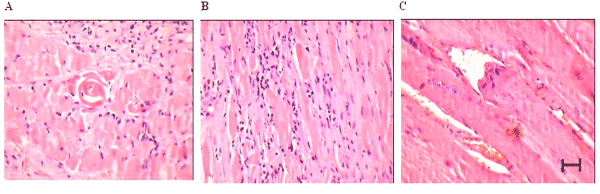

| Figure 1: Hematoxylin and Eosin staining of ischemic hind limb muscle sections at day 20 post-surgery in (A) PBS treated (B) EPC treated (C) eNOS-EPC treated group. Severe muscle necrosis, atrophy and inflammation are observed in PBS treated rabbits. EPC and eNOS-EPC treated animals show a significant reduction in muscle necrosis and atrophy in comparison to the PBS treated animals. |